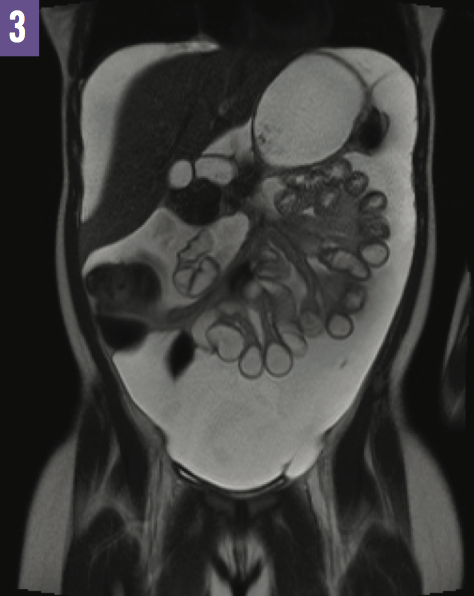

Diagnostic tests. Abdominal ultrasonography was performed, the results of which confirmed the presence of diffuse ascites (Figure 1). A radiographic shunt series and computed tomography scans of the brain without intravenous contrast (Figure 2) were obtained, the results of which confirmed stable placement of the VP shunt. Findings of abdominal and pelvic magnetic resonance imaging (MRI) were normal and did not demonstrate an abdominal pathology other than the marked ascites visualized within the peritoneal cavity (Figure 3).

Figure 3: Marked ascites were visualized within the peritoneal cavity on MRI.